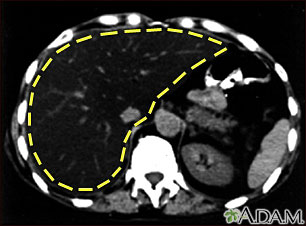

A CT scan of the upper abdomen showing a fatty liver (steatosis of the liver). Note the liver enlargement and dark color compared with the spleen (gray body in lower right).